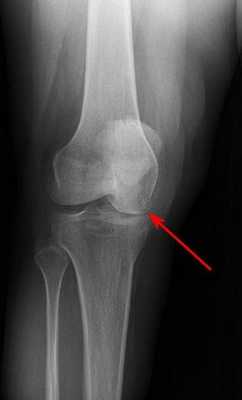

На снимке можно увидеть признаки асептического некроза внутреннего мыщелка бедренной кости.

Постепенно, с развитием заболевания может наблюдаться сужение суставной щели, сопряженное с травмированием хрящевой ткани сустава.